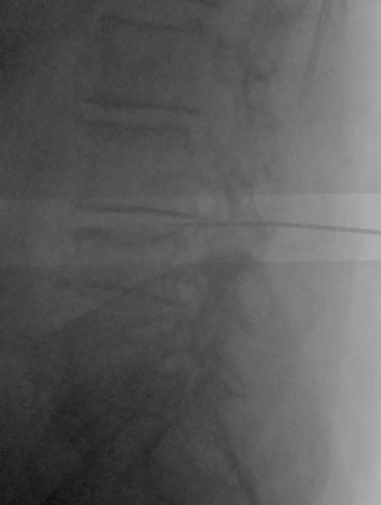

腰痛の根本原因でもある「腰椎椎間板ヘルニア」を取り除くため、症状のあるL3/4の1か所に「PLDD(経皮的レーザー椎間板減圧術)」を行いました。PLDDは、背中からレーザーファイバーが通った針を刺し、飛び出した髄核にレーザーを照射する治療法です。画像は実際、今回の患者さんに施術している様子です。